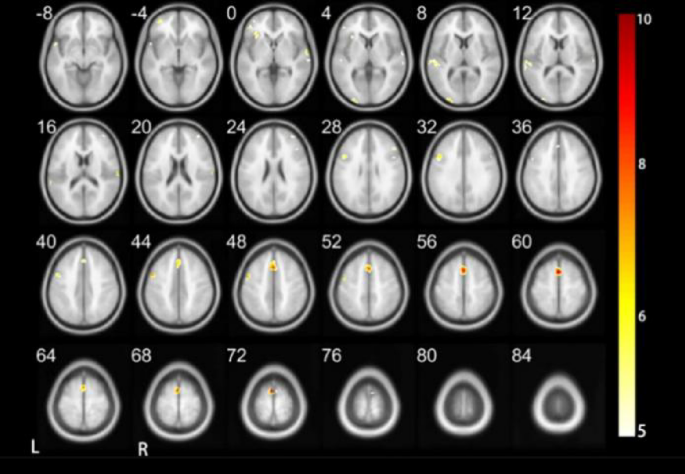

As depicted in Figs. 4 and 5; Tables 4 and 5, distinct patterns of neural activation were observed during the execution of the Vocal Tone 2 task in DC when compared to HC. Specifically, in DC, there was bilateral activation in the middle occipital gyrus, precentral gyrus, and supplementary motor area. These regions are critical for processing auditory and motor aspects of speech.

In contrast, HC demonstrated a more diverse pattern of activation. The right perisylvian cortex, left middle occipital gyrus, right middle temporal gyrus, left inferior frontal gyrus (triangular part), left precentral gyrus, right supplementary motor area, left middle frontal gyrus, and superior parietal gyrus are included. These findings indicate a broader neural engagement in the processing of vocal tones, possibly reflecting the integration of auditory, motor, and linguistic information.

Upon comparative analysis, notable differences in neural activation patterns were observed between the two groups. DC did not exhibit activation in several key areas associated with language processing and auditory perception, including the perisylvian cortex, middle temporal gyrus, triangular part of the inferior frontal gyrus, middle frontal gyrus, and superior parietal gyrus. Conversely, for regions such as the middle occipital gyrus, precentral gyrus, and supplementary motor area, there was bilateral activation in DC, whereas in HC, activation was predominantly observed in the left hemisphere. These discrepancies underscore the adaptive changes in neural processing strategies employed by DC in the perception and execution of vocal tones. The bilateral activation patterns in DC suggest a compensatory mechanism that may facilitate tone recognition and production in the absence of typical auditory input. Valuable insights into the neural plasticity associated with auditory deprivation and its implications for speech and language development have been provided.